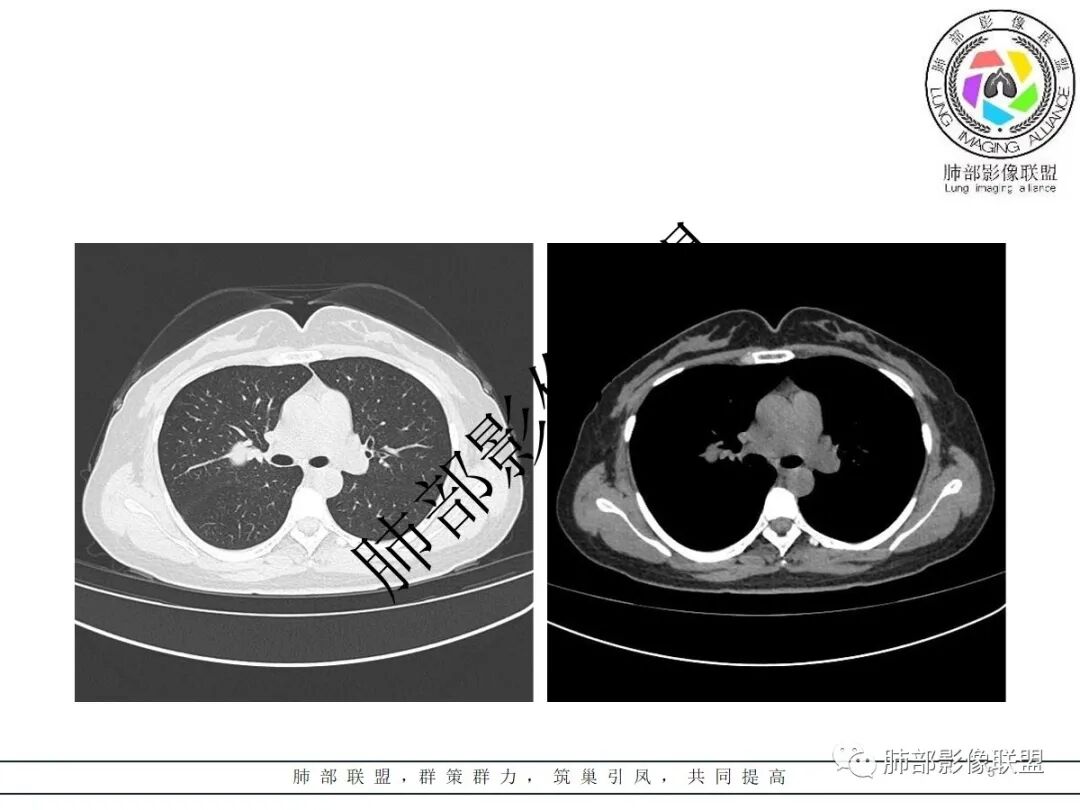

右肺门类圆形实性肿块,边缘光滑,无分叶毛刺,跨叶,推移血管,密度均匀,增强延迟强化相对明显,未见坏死及血管造影征。

2.右肺水平叶裂斜叶裂肺门交界区类椭圆形块影,表面光整,未见分叶毛刺及棘状突起,未见邻近结构牵拉。与邻近支气管无关联。

3.病灶密度均匀,未见液化坏死、钙化及脂肪低密度。轻度强化,可见纤细血管影蜿蜒穿行。右肺动脉推移变形,未见侵入或充盈缺损。

4.灶周未见磨玻璃晕或极低密度影环绕。右肺下叶背段胸膜下见微小实性密度结节影,边界清楚。

5.双肺门及纵隔未见增大淋巴结。双侧胸腔未见积液。